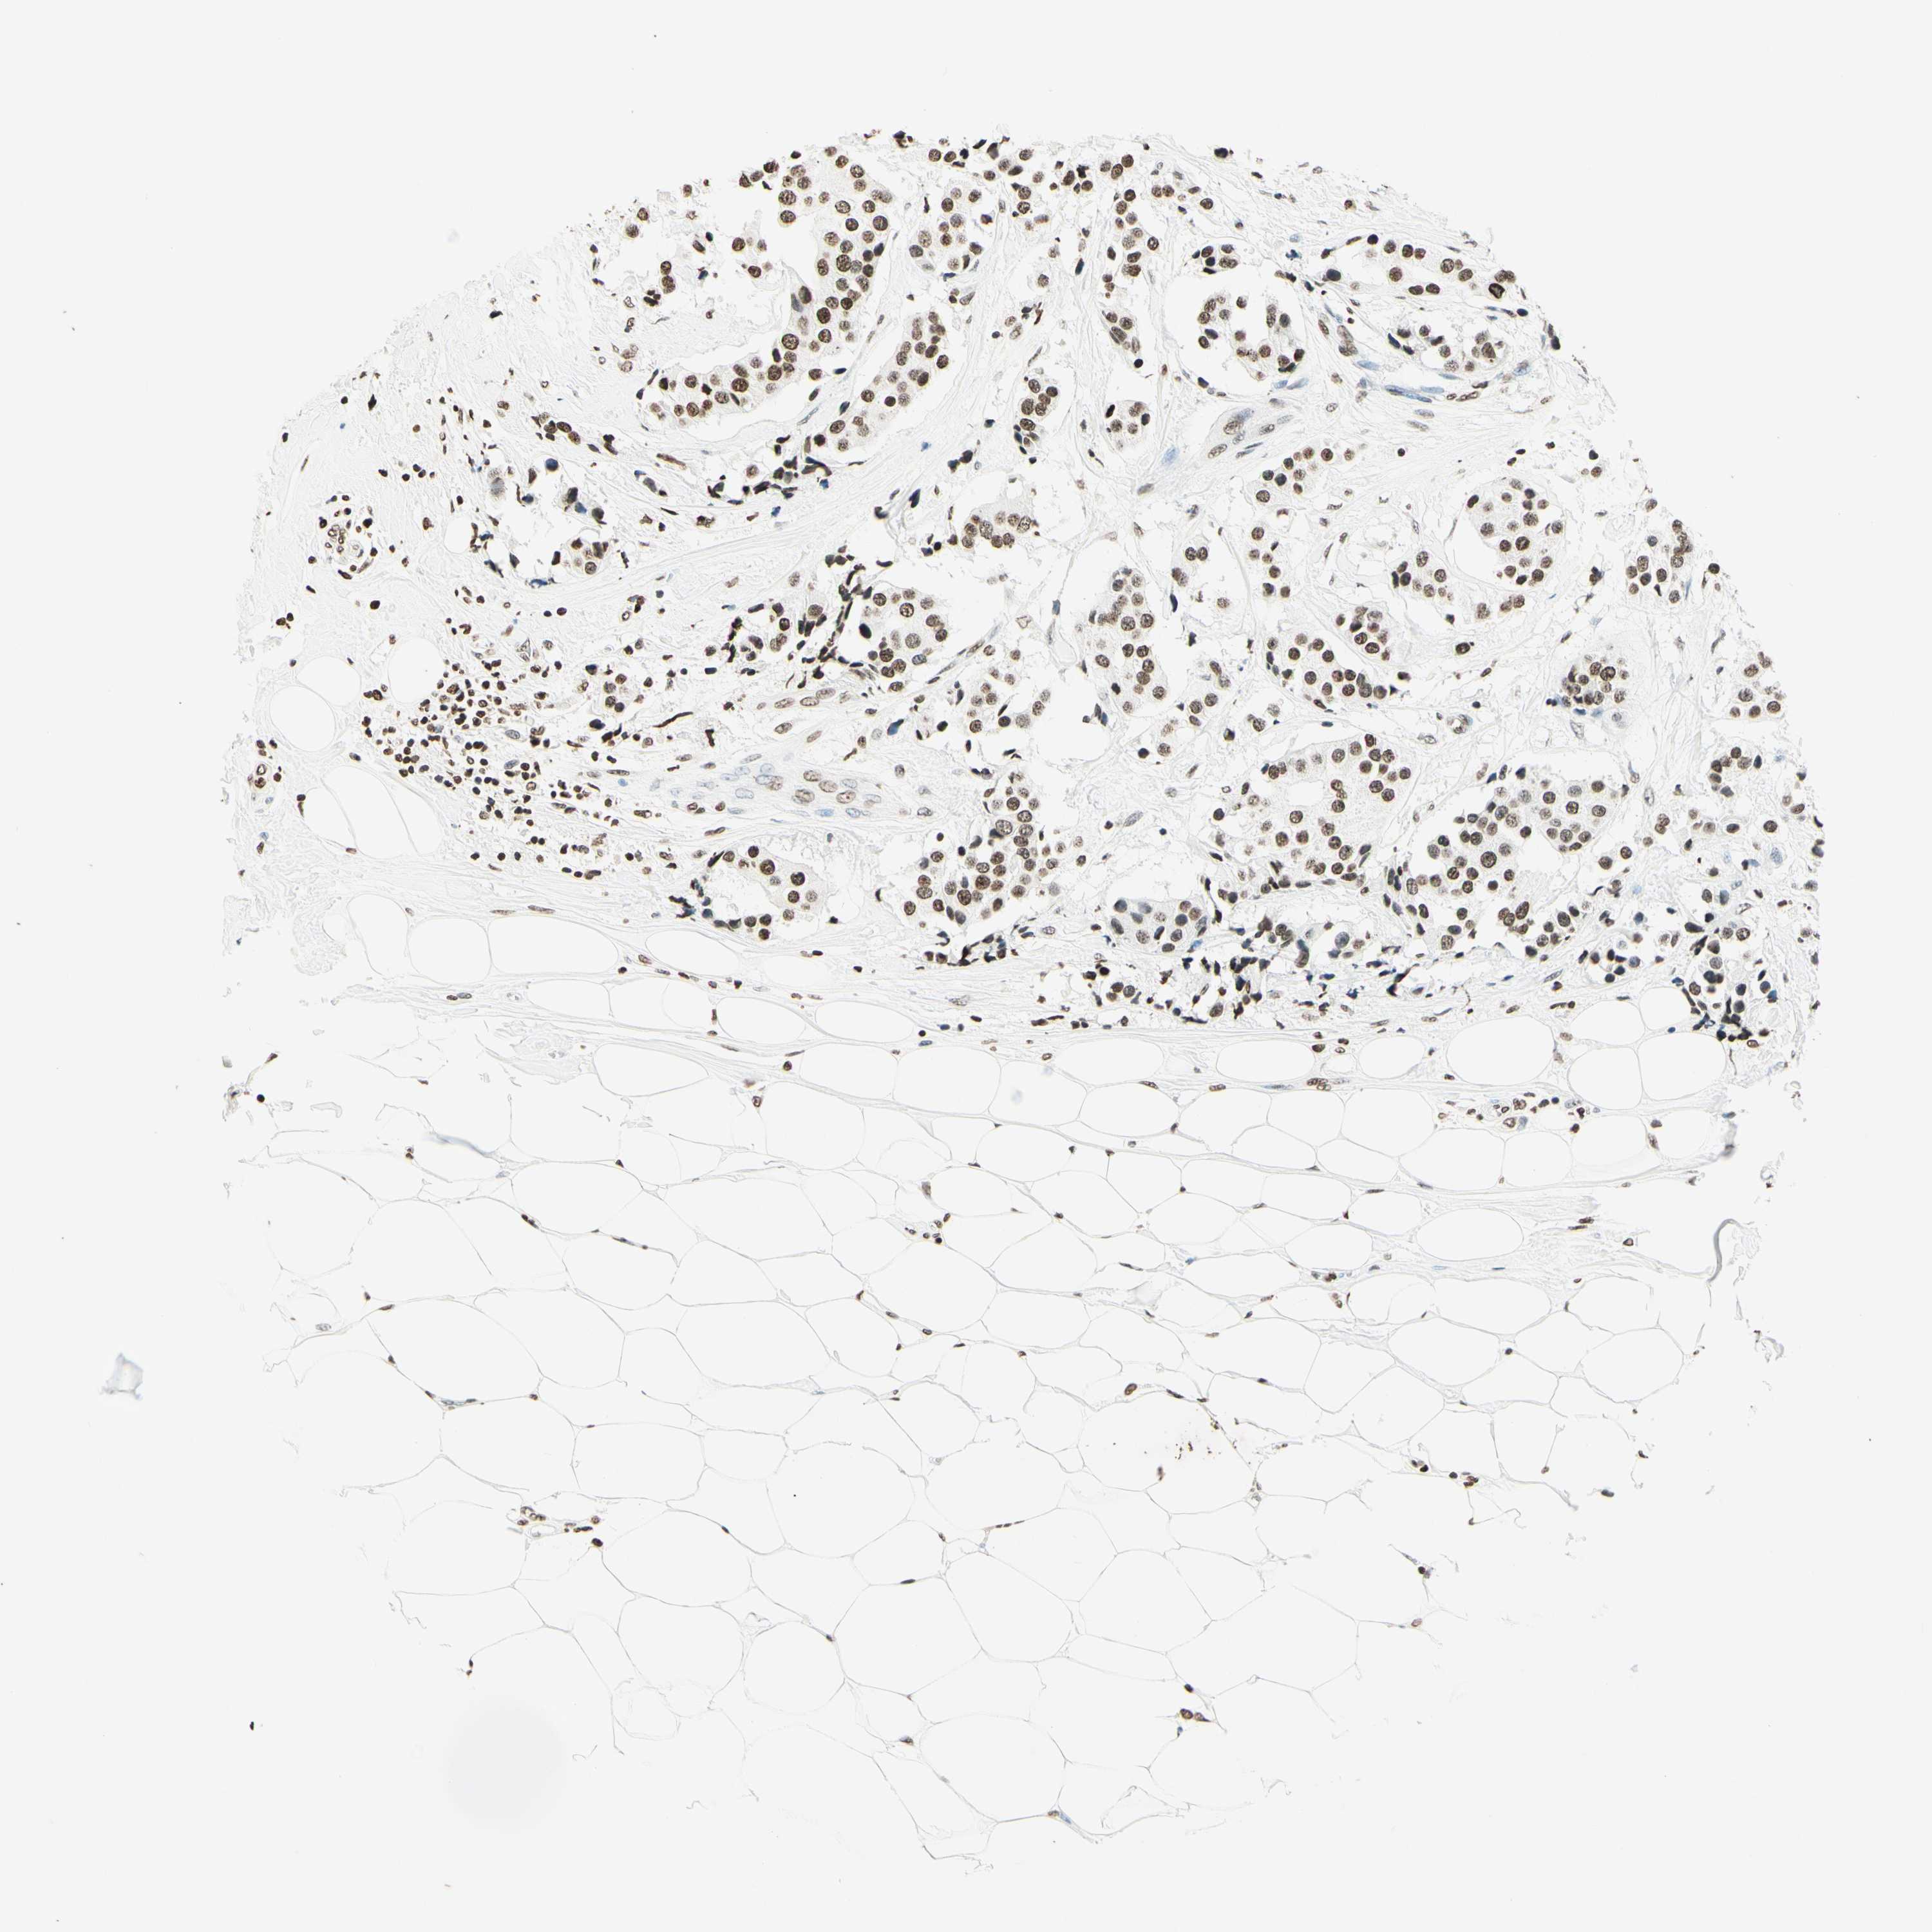

MSH2

CANCER BREAST CANCER Show tissue menu

BRCA TCGA BRCA VALIDATION PROTEIN EXPRESSION

Breast cancer

Human cancer